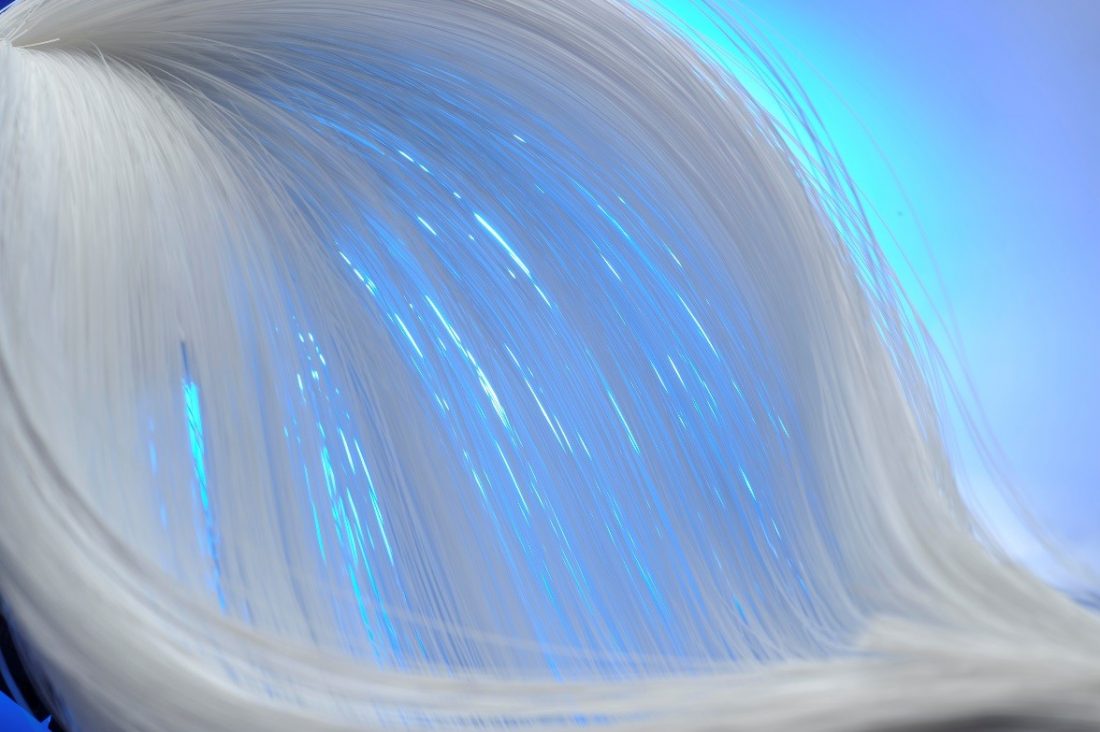

人工心肺のフィルターに使われる中空糸膜

中空糸膜フィルター(写真提供:DIC株式会社)

人工心肺の重要なパーツとして、血液に酸素を送る役割を果たすのが中空糸膜フィルターです。中空糸は、とても細いストロー状の糸の壁に小さな穴がたくさん空いています。中空糸を束ねてフィルターの仕事をするのが中空糸膜フィルターです。

私達の体には動脈と静脈が張り巡ぐらされています。動脈を流れているのは、肺から送り込まれる酸素や肝臓に送られる栄養素を含んだ血液を体の隅々まで送り届けます。静脈は体中の二酸化炭素を回収して、再び肺などへ送り届ける役割を果たします。